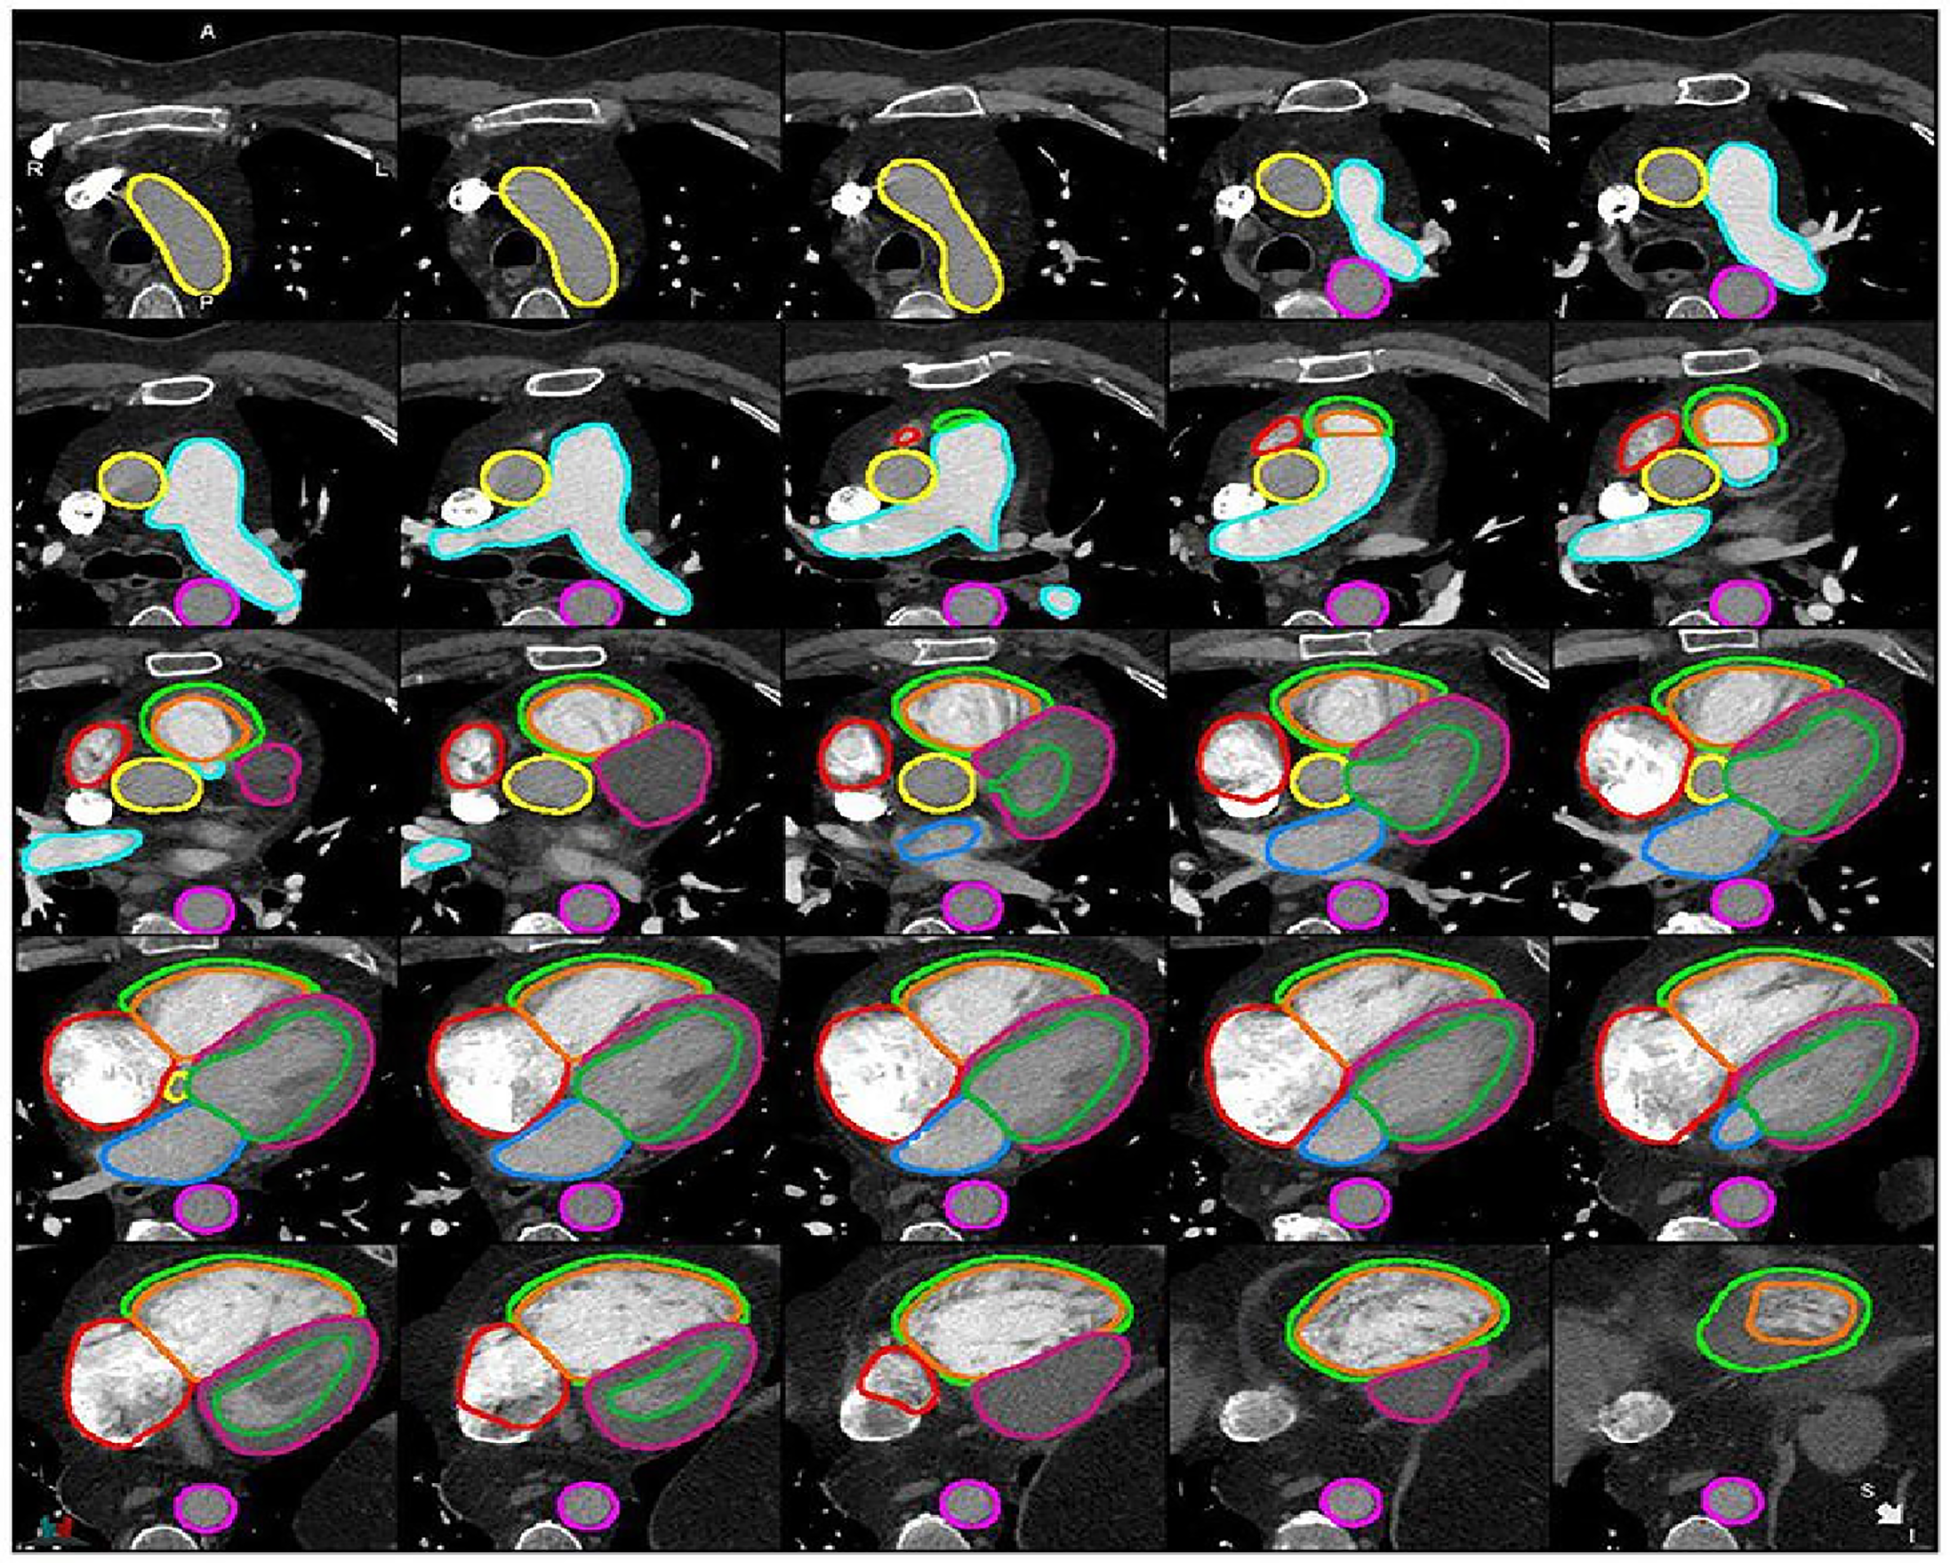

Segmentation refers to the process of delineating (or “contouring”) the edges of features on images. The features in question can be anatomical structures (such as the cardiac chambers) or pathological lesions (such as an area of myocardial infarction). Cardiac structures segmentation helps in the assessment of cardiac structures (Figure 1) and can assist with earlier detection of cardiac abnormalities (1, 5, 7–9). Traditionally, segmentation has been performed manually by radiologists. This process is time-consuming, subjective and prone to high levels of intra- and inter-observer variability. The application of artificial Intelligence (AI) to cardiac segmentation is of growing interest and offers potential improvements to efficiency and reliability compared to manual segmentation alone (10, 11). Furthermore, it was shown that the variability between observers and between an observer and an AI segmentation is similar (6). Recent years have seen a shift towards machine learning (ML) as the approach of choice for segmentation tasks. ML describes the process by which algorithms automatically identify patterns in data in order to make decisions or predictions when faced with new data. Deep learning (DL) is a subtype of ML in which multiple layers of algorithms—typically neural networks—are utilised, enabling the identification of more complex patterns and the generation of more accurate decisions (12, 13). Supervised DL depends on providing algorithms with accurate data for training, such as CT images labelled with manual segmentations by radiologists (6). Segmentation quality can be evaluated by comparing the degree of similarity between the DL and manual contours using either region-based indicators [such as the Dice similarity coefficient (DSC) or Jaccard index] or surface distance indicators (such as the Hausdorrf distance) (14).

Figure 1

Example of cardiac structures’ segmentation on CTPA images (6). Ascending aorta (yellow), pulmonary artery (light blue), descending aorta (pink), right atrium (red), RV epicardium (light green), RV endocardium (orange), LV epicardium (purple), LV endocardium (green), left atrium (blue).